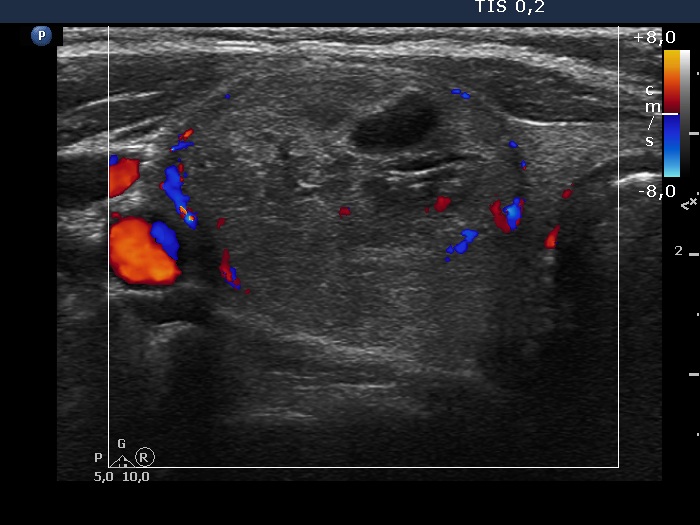

Right lobe, transverse scan, color Doppler mode. The nodule has perinodular blood flow.